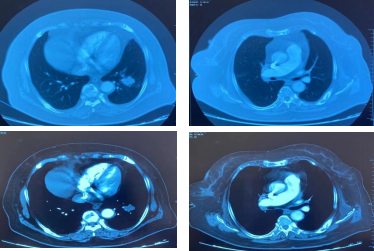

影像学-增强CT检查:治疗2周期后,左肺病灶明显缩小达52.9%,疗效评估为PR。

CT检查——治疗2周期后

治疗6周期后,左肺病灶明显缩小达58.6%,疗效评估为PR。

CT检查——治疗6周期后

治疗8周期后,左肺病灶较前增加,疗效评估为PD。

CT检查——治疗8周期后

综合来看此次治疗过程中,靶病灶变化情况先缩小再增大。